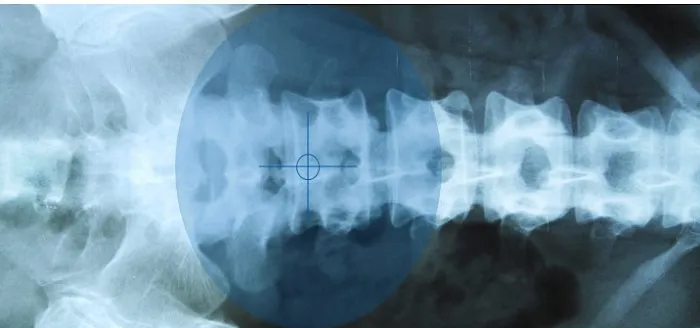

Chiropractic care is a primary healthcare profession focused on the diagnosis, treatment, and prevention of disorders of the neuromusculoskeletal system, particularly the spine. The core principle of chiropractic care revolves around the body's remarkable ability to heal itself, provided there is proper alignment and function of the spine, which houses and protects the central nervous system. When spinal segments become misaligned, known as subluxations, they can interfere with nerve communication, leading to pain, reduced mobility, and various health complaints. Chiropractors at Spine Health Centers utilize a range of gentle yet effective techniques, primarily spinal adjustments, to correct these misalignments. By restoring proper spinal mechanics, these treatments aim to alleviate pain, improve nerve function, enhance mobility, and support the body’s innate healing processes. This holistic approach focuses on identifying and addressing the root cause of your discomfort, rather than simply masking symptoms, paving the way for lasting relief and improved overall health.

Spine Health Centers offers a comprehensive suite of services dedicated to diagnosing, treating, and preventing a wide array of spinal conditions and musculoskeletal issues. Their integrated approach aims to provide holistic relief and long-term wellness. While specific details for "Spine Health Centers" in North Hollywood require direct consultation, based on the general scope of "Spine Health Centers" and "chiropractor" practices in California, a typical range of services would include:

- Herniated and Bulging Disc Treatment: Specialized therapies aimed at reducing pressure on spinal discs and promoting healing.

- Spinal Decompression Therapy: Non-surgical treatment that gently stretches the spine to relieve pressure on compressed nerves and discs.